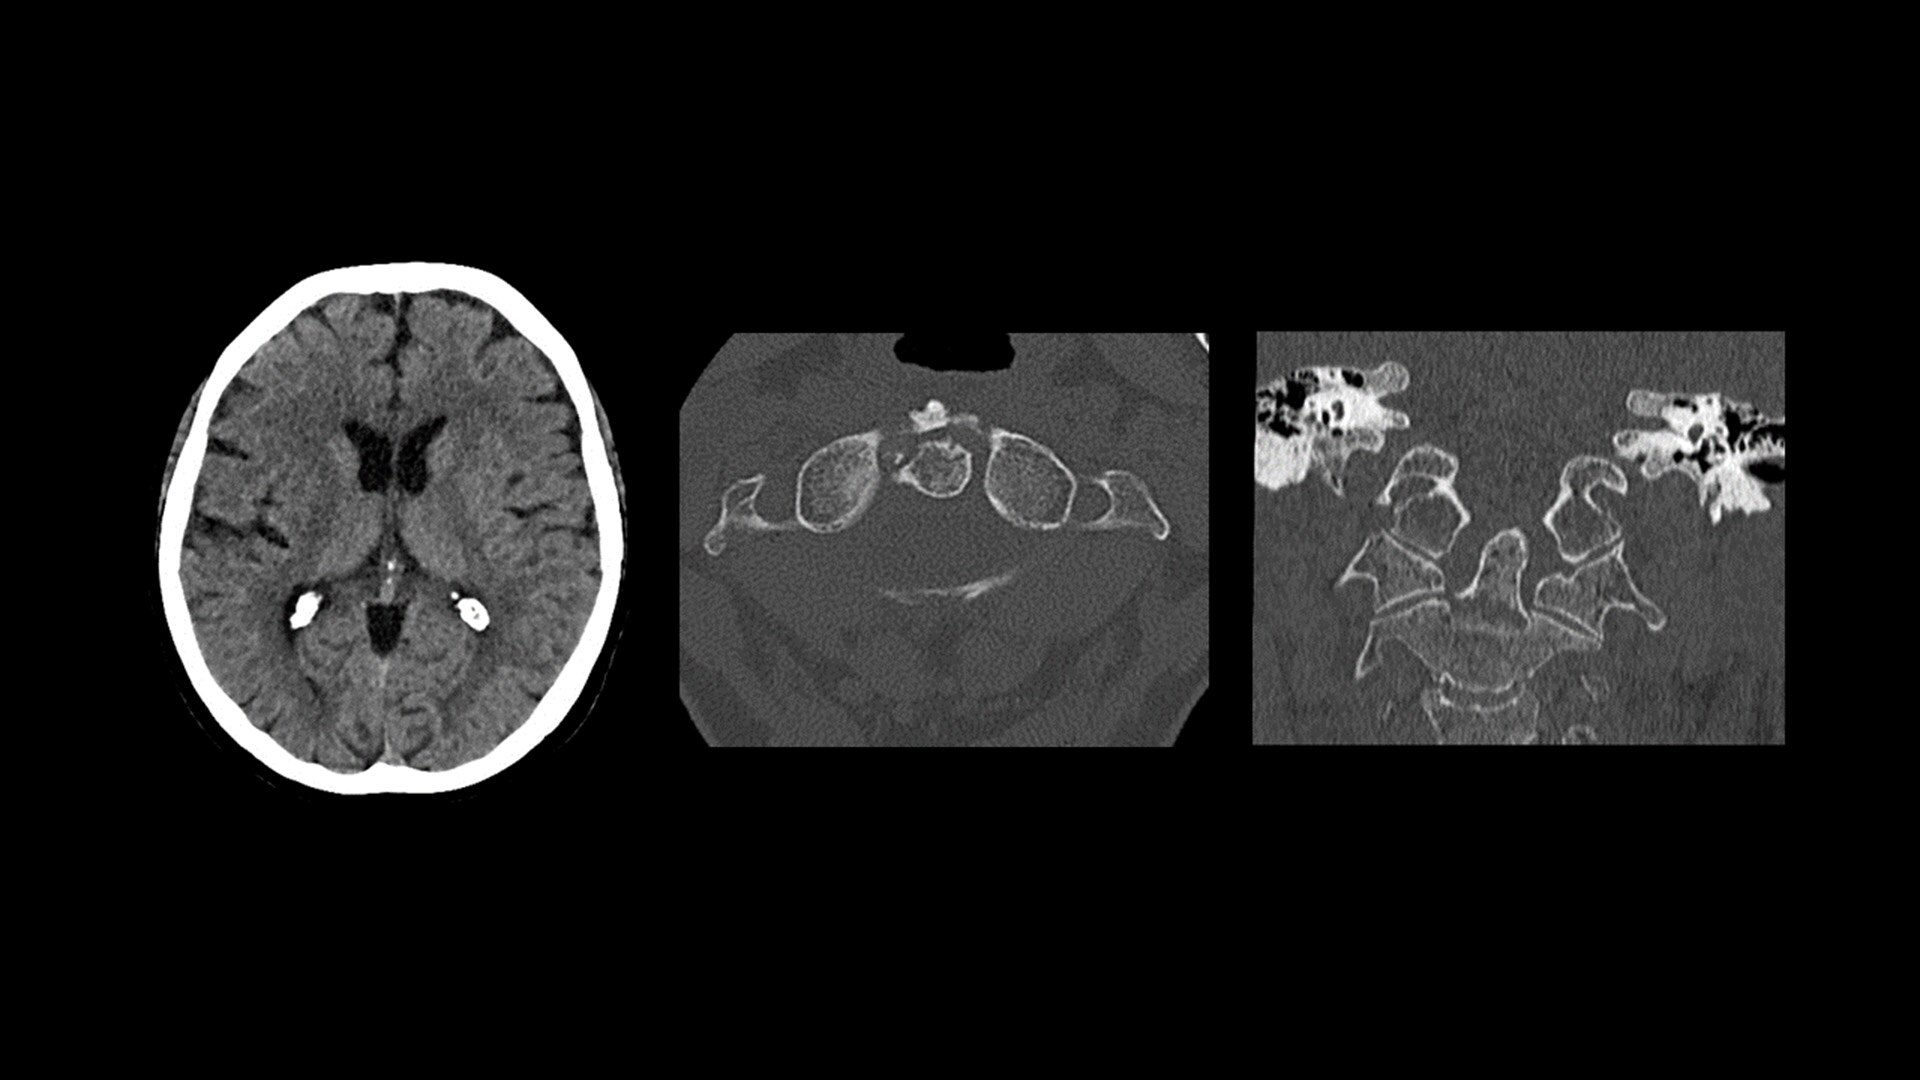

Unlimited 1-Beat Cardiac is designed to provide consistent, high-quality imaging for accurate diagnoses, even in challenging patients with atrial fibrillation, breath-holding difficulties, heavily calcified coronaries, in-stent restenosis, and situations where an ECG trace is unavailable.